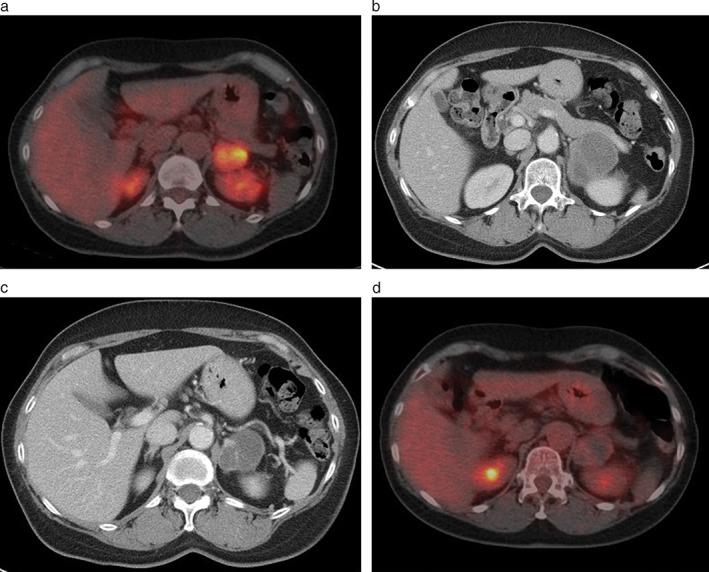

Pleomorphic carcinoma (PC) of the lung is a rare type of non-small cell lung cancer, exhibiting aggressive behavior and resistance to chemotherapy and radiotherapy. A previous study reported that PCs expressed high levels of PD-L1, suggesting the potential efficacy of immune checkpoint inhibitors in these tumors. We retrospectively reviewed the clinical records of three patients with PC of the lung treated with nivolumab: a 59-year-old woman (Case 1), a 66-year-old man (Case 2), and an 83-year-old man (Case 3). PD-L1 was highly expressed in their tumor cells. Two cases showed a partial response with long progression-free survival. However, in Case 2, brain and bone metastases progressed during nivolumab treatment in spite of high PD-L1 expression. This case series indicates that nivolumab is effective to some extent for PC of the lung. However, the clinical course of patients treated with nivolumab should be carefully observed, even when PD-L1 is highly expressed.

肺多形性癌(PC)是一种罕见的非小细胞肺癌,表现出侵袭性行为和对化疗和放疗的耐药性。先前的一项研究表明,PCs 表达高水平的 PD-L1,提示免疫检查点抑制剂在这些肿瘤中的潜在疗效。我们回顾性分析了三例接受纳武利尤单抗治疗的肺 PC 患者的临床记录:一名 59 岁女性(病例 1)、一名 66 岁男性(病例 2)和一名 83 岁男性(病例 3)。他们的肿瘤细胞中 PD-L1 高表达。两例患者表现出部分缓解和较长的无进展生存期。然而,在病例 2 中,尽管 PD-L1 高表达,但在纳武利尤单抗治疗期间脑和骨转移仍进展。本病例系列表明,纳武利尤单抗对肺 PC 具有一定的疗效。然而,即使 PD-L1 高表达,接受纳武利尤单抗治疗的患者的临床过程也应仔细观察。